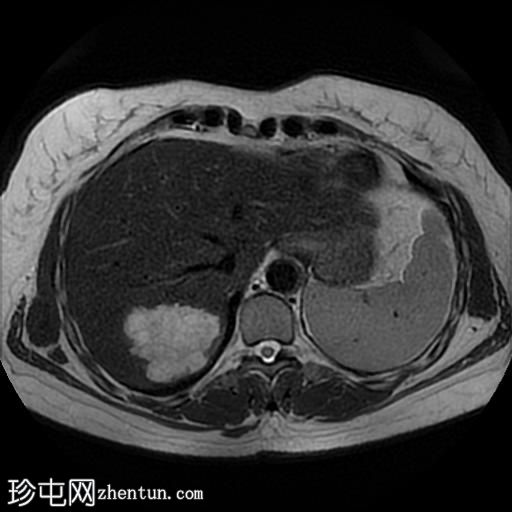

轴位

T2加权像

肝脏第7段可见一边界清晰的分叶状肿块。T1加权像呈低信号,T2/T2脂肪抑制序列呈高信号,动脉期呈不连续结节状周边强化,门静脉期呈向心性强化,延迟期完全强化。DWI序列呈高信号,ADC值呈混合信号。